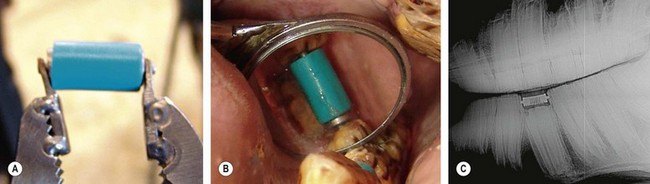

The orthodontic principles of tooth movement are at work on horses that develop abnormal wear patterns on exposed dental crowns. Dental elongations place stresses on the tooth that can result in abnormal movement. The general laws of biomechanics apply to movement of teeth. Alveolar bone is reabsorbed when the root and reserve crown maintain compressive force on the periodontal ligament. New alveolar bone is deposited when stretching forces act on bone. However, these laws are subject to numerous variations and exceptions when factors such as magnitude, direction, and duration of force are introduced.1 Dental cementum has the inherent tendency to resorb when pressure is applied to it but to a lesser degree than bone. Dental floating and equilibration are forms of orthodontic correction used in an attempt to reduce abnormal forces placed on teeth and thus improve occlusion. The application of orthodontic wire, springs, coils, arch bars, bands, brackets, incline planes, and elastics has been used in correcting common malocclusion problems of horses (Fig. 19.1).25

Fig. 19.1 (A) Orthodontic spring device used to spread 307 and 309 to allow room for an impacted 308 to erupt. (B) Intra-oral mirror used to visualize the orthodontic spring in the 308 position. (C) Lateral radiograph of impacted 308 with orthodontic spring in the dental space.

(Courtesy of B.W. Fletcher DVM.)